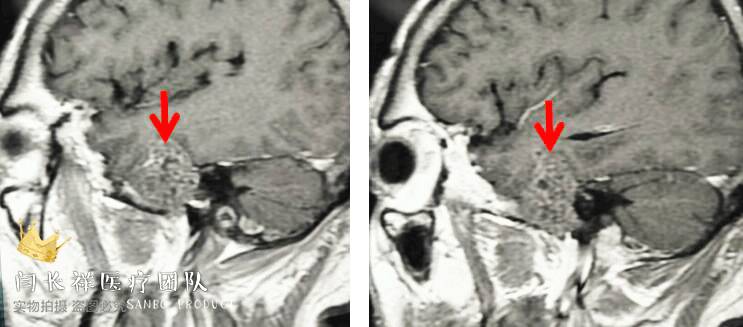

中颅窝-颞下窝占位

术前矢状位CT。

术前MRI矢状位T1增强。

术前MRI冠位T1增强示病灶主体位于硬膜外,侵蚀中颅窝底骨质并朝颞下窝、翼腭窝生长。